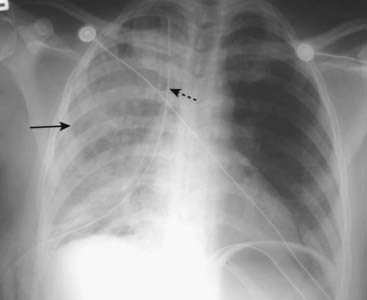

image Abnormal accumulations of fluid begin in the dependent portions of the pericardial space, which, in the supine position, is posterior to the left ventricle (Fig. 9-2A).

image As the pericardial effusion increases in size, it tends to accumulate more along the right heart border until it fills the pericardial space and encircles the heart (Fig. 9-2B).

image CT scans can demonstrate small pericardial effusions, although pericardial ultrasonography is usually the imaging study of first choice. Conventional radiographs are poor at defining a pericardial effusion.

image

Figure 9-2 Pericardial effusions, small and large.

A, Fluid first begins to accumulate in the dependent portions of the pericardial space which is posterior to the left ventricle in the supine position (solid white arrow). B, As the effusion increases in size, it fills the pericardial space and encircles the heart (dotted white arrows). Conventional chest radiographs may show an enlarged cardiac silhouette but cannot differentiate the density of the heart from the effusion.